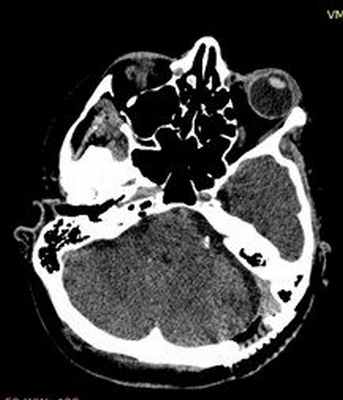

Рис. 4. Установленные тефлоновые прокладки на контрольной СКТ головного мозга